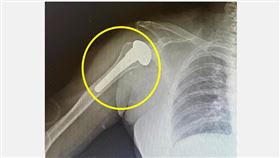

肩膀痛以為50肩!50歲女運將關節竟全磨損

台中一名50歲的女計程車司機,因長期上班手握方向盤,...

64歲徐乃麟(乃哥)保養有方,他接受《三立新聞網》專...

2024/03/12 08:50